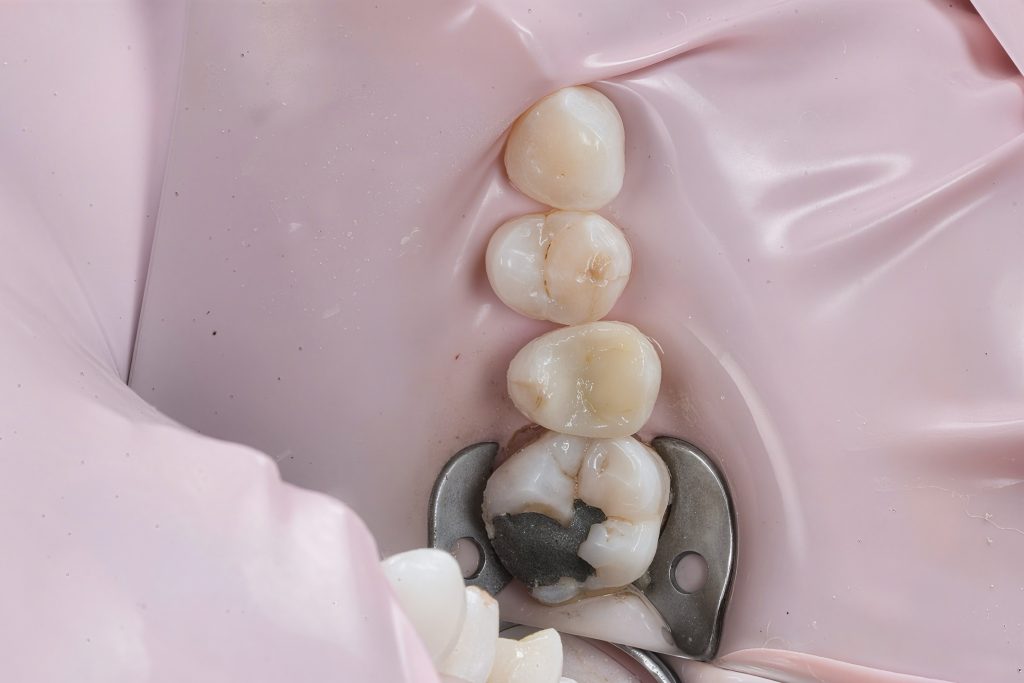

1. Isolation

Rubber dam isolation achieved using clamp stabilization to maintain a dry and clean operative field – essential for adhesive dentistry (Fig 1–2).

- Rubber dam isolation